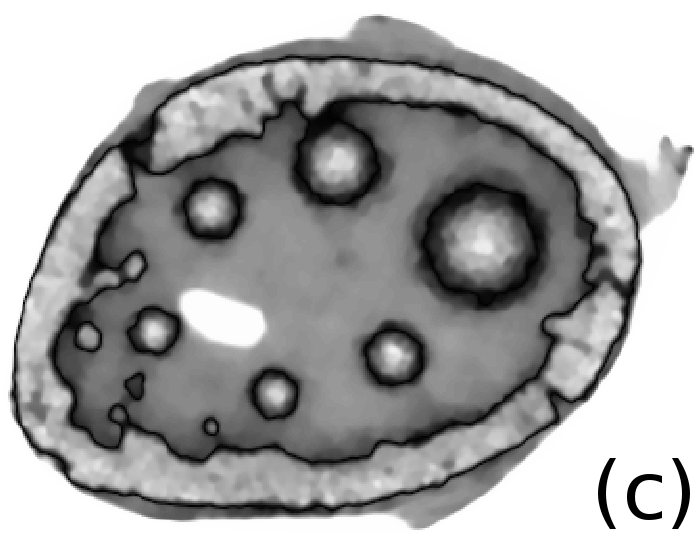

To simulate emission tomography reconstruction we designed a more realistic phantom from the high-quality X-ray scan of a mice bone. The data was acquired on a Nikon Metris Custom Bay cone-beam scanner at the Henry Moseley Manchester X-ray facility, and was reconstructed with the Feldkamp algorithm (see Fig. 7 (left)). We thresholded the obtained reconstruction and added six gaussians with various kernel widths (see Fig. 7 (middle and right)).

To simulate PET projection data we used NiftyRec [22], a software for tomographic reconstruction, providing GPU-accelerated reconstruction for emission and transmission computed tomography. The phantom size is pixels and 300 projections was simulated. Poisson noise was added to projections with an expected number of photon counts in total. Twenty noise realizations were simulated to estimate methods quantitatively. The point spread function of the PET system was modelled (with convolution of the sinogram columns with a Gaussian of full width half maximum of three pixels) in the projection and back-projection operations. No scatter was simulated in this study. For our experiments (see algorithm 2) we performed 130 MLEM iterations and 5 inner iterations (denoising step).

To quantify obtained reconstructions we used averaged over all noise realizations RMSE (23) values in the bone region (BR) and in Gaussian regions (GR). All regularization parameters were carefully selected by comparing the mean of all RMSE values over all noise realizations in GR and BR (see Fig. 8).

After estimation of regularization parameters we performed twenty reconstructions for each method with various Poisson noise distributions. The mean values for GR and BR over all noise realizations are shown in Fig. 9. This result proves that the EL penalty is very successful in resolving smooth features (six Gaussians in this case) and also quite competitive for the BR (lower RMSE value than for TV).

In Fig. 10 and 11 one can notice that the BR is very smooth for TV and TV- penalties and some long-wave oscillations can be seen in the reconstructed image with EL penalty. This result corresponds to the expected behaviour of the EL penalty. We note here that the phantoms background (see Fig. 7) is not as flat as TV and TV- penalty recovered it. Furthermore, a small size dot-like feature (approximately in the centre of the phantom) is almost smoothed out with TV and TV- recovery. However, it is visible and well recovered with EL penalty. The sharp features, overall, are reconstructed very well with MLEM-EL method and seem even sharper compare to other methods (see the bone outer rim in Fig 10).